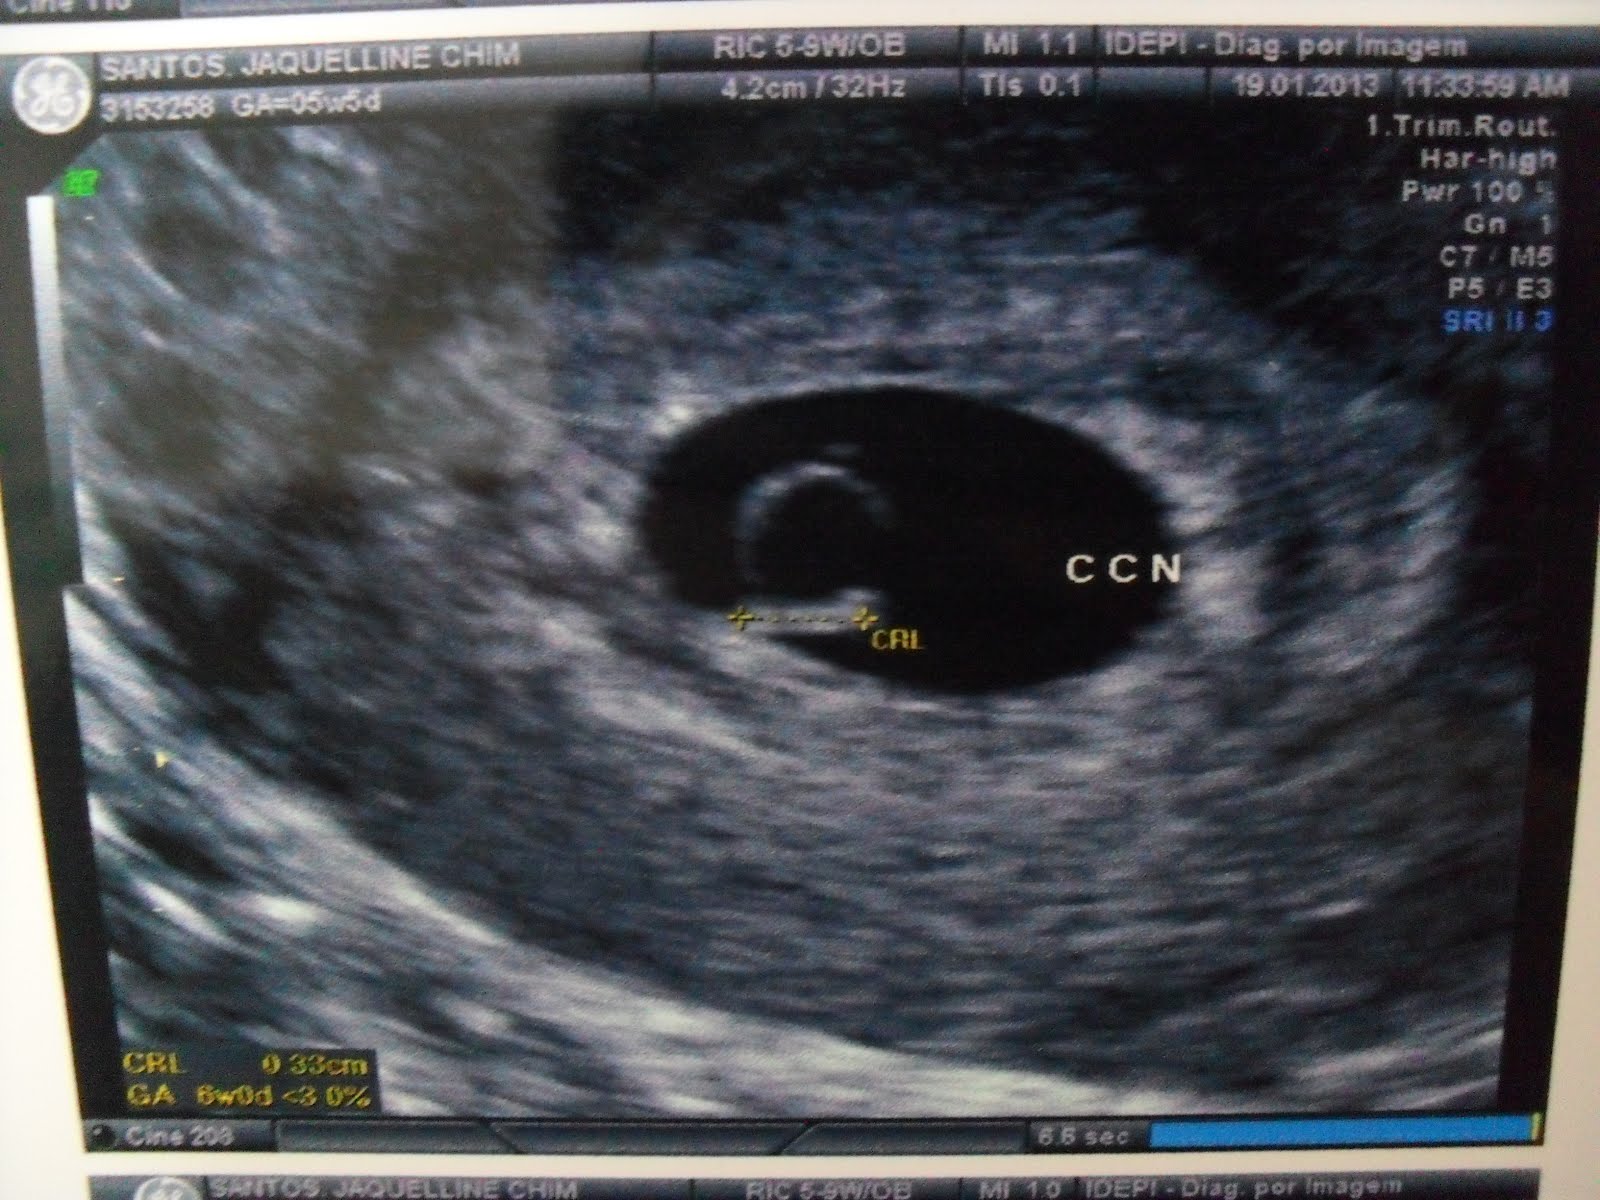

Felizmente a atendente era boazinha e conseguiu trocar a guia com facilidade, e logo entramos. Me troquei e toda aquela ladaiinha e fomos ver nossa alegria! Primeiro mostrou o saco gestacional, disse que ovulei do lado esquerdo (juuro que eu já sabia gente, é serio!era desse lado que doía!!) mostra todas as paredinhas, sem descolamento, sem hematomas, sem nada pra me preocupar. Mostra o saco gestacional (17mm, enoooorme! Sério, é muito grande pro espacinho que o bebê ocupa, haha!) e daí eu vejo, aquela coisinha minuscula, piscando!!Sim, eume assustei, achei que não teria coraçãozinho piscando ainda, achei que nem daria pra ver o baby, só o saquinho e a vesicula lá, mas não, tinha uma coisinha piscando!! O doutor era muito querido, começou a falar que ele tinha 3,3mm, que era literalmente um pinguinho de gente! Aí ele falou pra gente tentar ouvir o coraçãozinho, tava muuuito muuuito baixinho, disse pra gente não se preocupar porque esse período é quando os batimentos são mais baixos e devagares da gestação toda, que com umas 9 semanas é o auge e que vai aumentar muuito! No laudo nem consta quantos bpm's foram, vamos ter que esperar!

Aí vai uma fotinho do nosso pinguinho de gente mais amado do mundo!